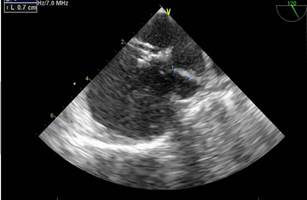

En subcostal 4 cámaras se observa CIA de 7 mm de diámetro con shunt de izquierda a derecha. (Figuras 2,3,4)

La distancia del defecto al plano valvular tricúspideo (borde anteroinferior) es de 11 mm. (Figura 5 )